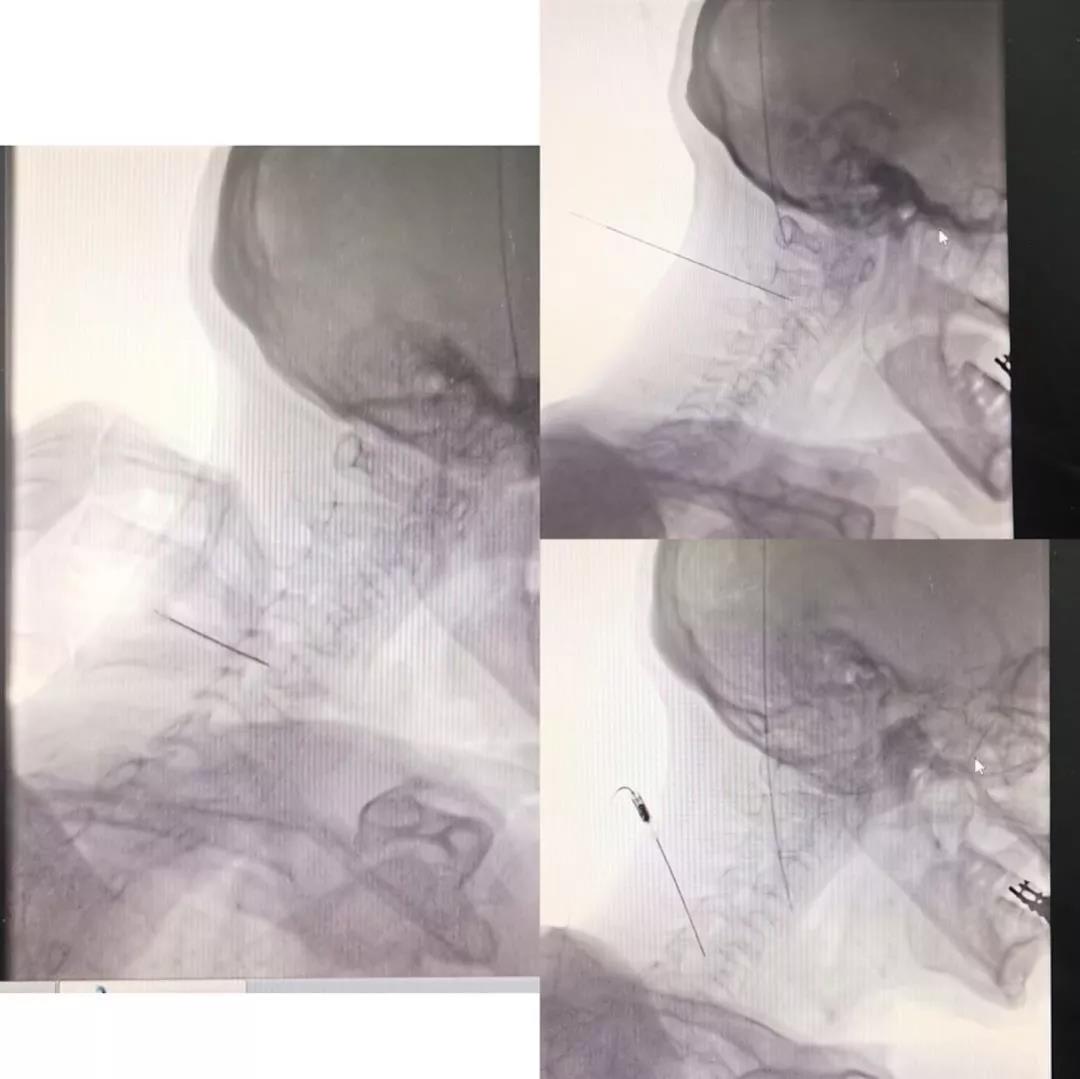

最终,吉大爷经贵州好友推荐到我院疼痛介入科住院治疗。经疼痛介入科张晨及张万云主治医师治疗,并进行相应阶段神经阻滞后,确定了患者的带状疱疹病毒损害的神经节段,经历一周的神经阻滞治疗,患者疼痛控制较好,但神经阻滞远期疗效仍待观察。综合患者病情考虑后,疼痛介入科两位主治医师为患者进行了“多颈段脊神经后支射频调制术”。术后病人疼痛控制满意,且长期服用的吗啡类药物也已停用,疼痛没有反复现象,VAS评分由7-9分降至1-2分。经过治疗后,吉大爷的生活质量有明显提高,不再忍受疼痛侵扰,出院期间也特地带领儿女感谢了疼痛介入科医护人员。